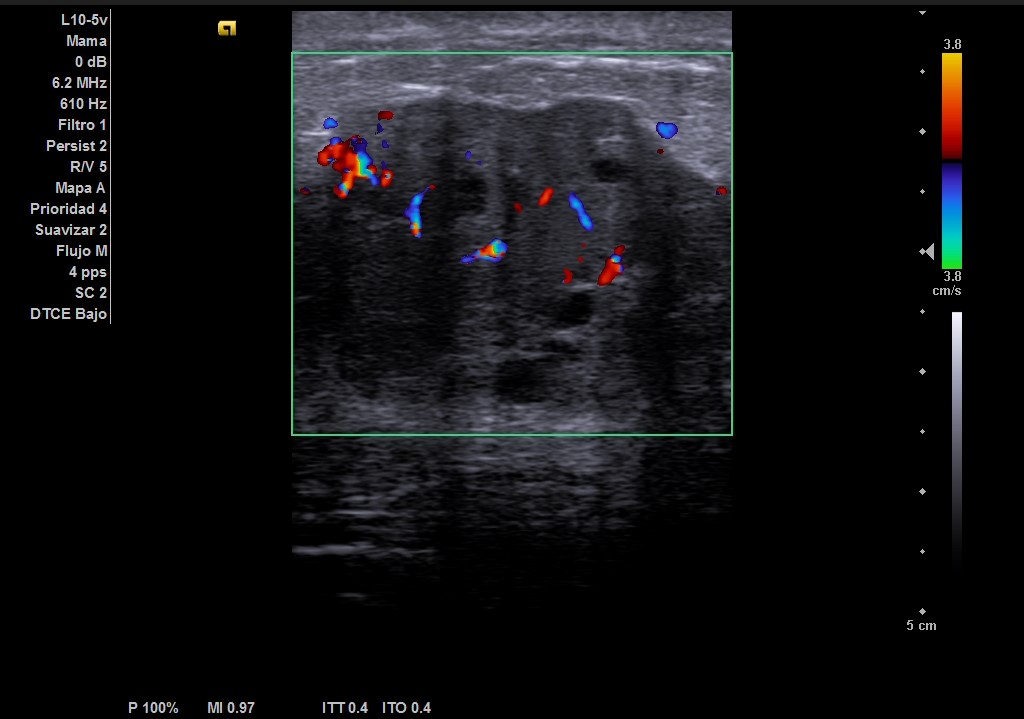

Ecografía: mama izquierda se observa tumoración hipoecogénica lobulada en cuadrante superior externo de aproximadamente 4 cm, heterogénea, que capta al Doppler color y dos adenopatías de aspecto reactivo en axila homolateral. Imagen sospechosa de malignidad.

Mamografía bilateral mama izquierda: masa mal definida de al menos 5 cm de diámetro, asociada a un engrosamiento cutáneo y trabecular difusos. Hallazgo sospechoso de malignidad. Adenopatías axilares izquierdas.

Ecografía de mama hospitalaria: Se confirma en mama izquierda masa sólida palpable de al menos 56 mm, de contorno mal definido, sospechosa de malignidad. Se realizará BAG ecoguíada, y adenopatías axilares izquierda de aspectos patológico. PAAF de ganglio izquierdo dirigida por ecografía: Citología positiva para malignidad. Compatible con metástasis de carcinoma. Biopsia BA Tipo histológico: Carcinoma infiltrante. Grado histológico: Grado III, pobremente diferenciado.